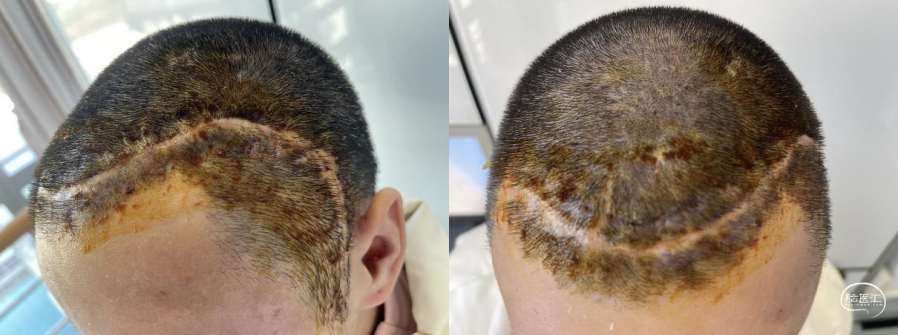

手术过程

可见角突处钛网凹陷,皮瓣状况良好。

治疗结果